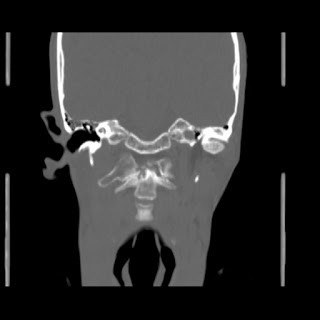

O/E images: